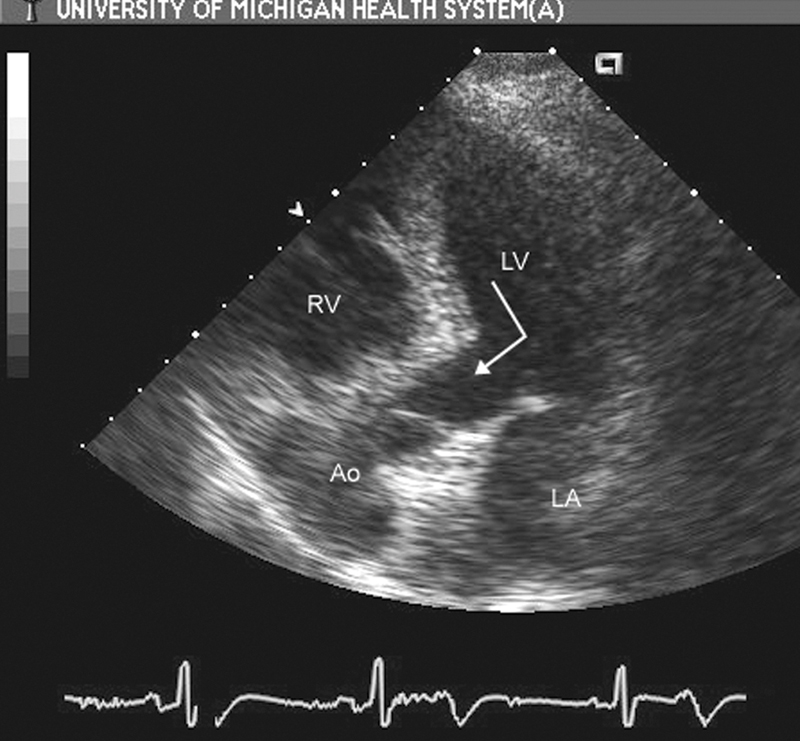

فحوصات تشخيصية لبعض امراض القلب والشرايين التاجية